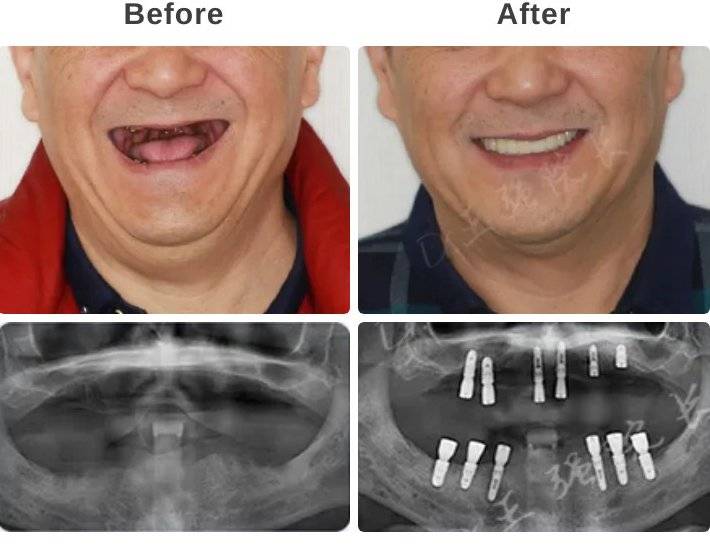

all-on-4种植牙让王伯伯重获新生牙齿真实案例_北京维尔口腔医院

避免做全口种植牙后悔来一波全口牙缺失种植案例供你参考

图片尺寸600x458